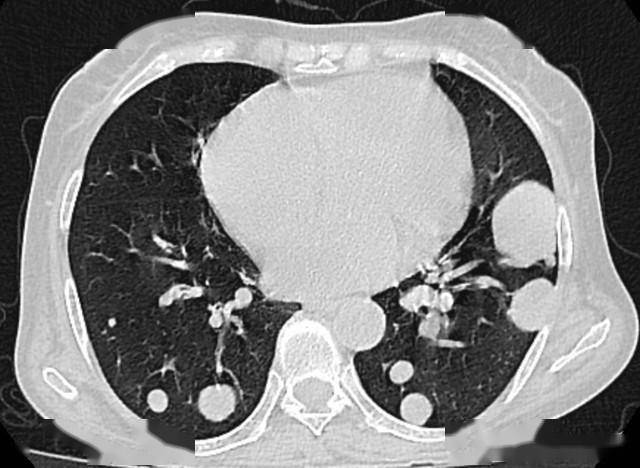

很多人一看到“肺结节”就联想到癌症,其实它只是影像学上的“小阴影”——简单说,就是CT片上肺部出现的、直径≤3cm的圆形或不规则病灶,可能是炎症留下的“疤痕”,也可能是良性肿瘤,只有少数会发展成癌症。

3. 密度异常:混合磨玻璃结节恶性概率最高

根据CT上的密度,肺结节分为实性结节、纯磨玻璃结节和混合磨玻璃结节。其中,混合磨玻璃结节(既有磨玻璃密度,又有实性成分)的恶性概率最高,可达60%。纯磨玻璃结节恶性概率较低,而实性结节中,良性的比例相对较高,但直径较大的实性结节也需警惕。

比如有人查出混合磨玻璃结节,直径1.2cm,医生建议手术切除,术后病理显示是早期腺癌,如果拖延下去,癌细胞可能会进一步扩散。